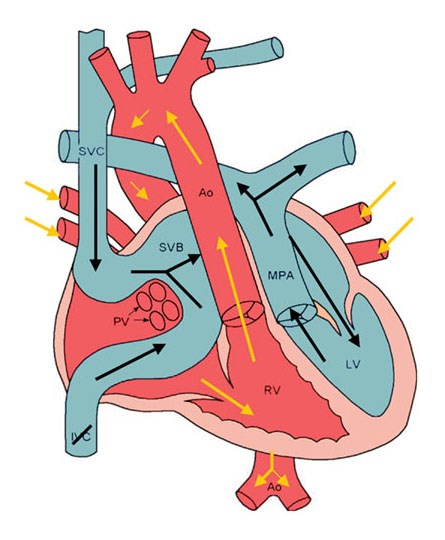

Overview

Package includes:

Days in hospital : 10 to 11 Days (For patient and one attendant)

Days in hotel : 14 Days (For patient and one attendant)

Room type in hospital : Shared

Room type in hotel : Private

Hotel category: Standard

Value added benefits of the BT Shunt: